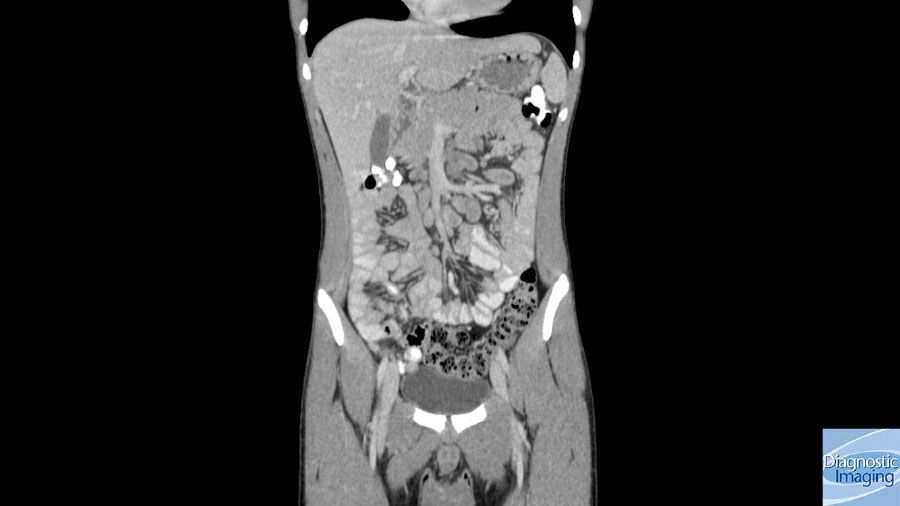

Case History: 45-year-old patient presented with history of abdominal discomfort.